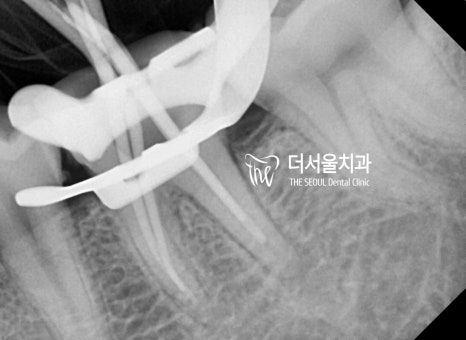

신경치료를 위해 치아 표면을 다듬고

작은 홀(hole)을 뚫었는데요.

음.. 크랙(crack)이 생긴 것을

육안으로 확인할 수 있었습니다.

금이 간 것은 방사선 촬영으로

확인하기가 쉽지 않기 때문에

의료진의 경험을 토대로 예측을 하거나

육안으로 관찰하는 수밖에 없죠.

성남치과 에서는 감염된 근관 내부를

깨끗하게 청소, 소독하고

충전재를 사용하여 내부 충전을 마쳤습니다.